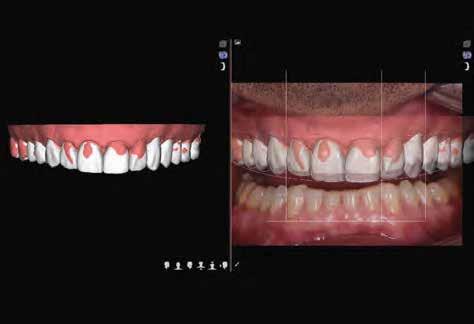

Dr. Miguel Stanley, dr. Ana Gomes Paz, dr. Inês Miguel (Portugália) Dr. Christian Coachman (Brazília) 1. ábra: Kiindulási állapot (frontális irányból). 2. ábra: A kiindulási állapotról okkluzális irányból készített felvétel (felső állcsont). 3. ábra: A kiindulási állapotról okkluzális irányból készített felvétel (alsó állcsont). 4. ábra: A kiindulási állapotról készült panorámaröntgen felvétel (2015).

2015-ben egy 47 éves férfi páciens állkapocs-ízületi panaszai miatt kereste fel a rendelőnket. Ezen felül esztétikai problémát jelentett számára, hogy az egyik felső nagymetszőfogán lévő héj eltört (1-3. ábrák). A klinikai és radiológiai vizsgálatot követően megállapítható volt, hogy a páciens kifejezett bruxizmusa miatt csökkent a harapási magassága, és jelentős mennyiségű saját foganyagot abradált el (4. ábra)

Szájterpesz használata mellett digitálisan intraorális fotók készültek a páciensről mind frontális, mind laterális és okkluzális irányokból. További fotók is készültek a páciensről egy digitális tükörreflexes kamera segítségével (frontális és laterális irányból, valamint 45 o-os szögből). Mindkét állcsontról digitális lenyomat készült egy intraorális szkenner segítségével (Care stream 3500). A maximális-interkuszpidációs helyzetet (IKP) szintén a Carestream 3500-as készülék felhasználásával rögzítet -

5. ábra: A mosolytervezéshez szükséges felvétel. A mosolygó páciensről az ajak- és a bucca eltartásával készített fotó.

6. ábra: Demonstrációs céllal bisz-akrilátból készített mock-up (Structur 3).

tük. Az új harapási magasságot a CAD/CAM szoftverben létrehozott virtuális artikulátor általunk meghatározott mértékig történő nyitásával határoztuk meg.

A kiindulási helyzet rögzítésére a DSD dinamikus dokumentáció protokollját használtuk. Egy okostelefon segítségével 4 különböző szögből videókat készítettünk, hogy később ezek alapján ki tudjuk alakítani a páciens legoptimálisabb mosolyát. A következő felvételek készültek: frontális irányú a mosolygó páciensről az ajkak és az orca eltartásával, majd az eltartásuk nélkül, továbbá oldalirányú felvétel, egy a homloktól az állcsúcs irányába mutató, és egy az okklúziós síkra merőleges irányból készült, illetve egy záró harapási helyzetben lévő hátsó fogakról (tükör nélkül).

Négy kiegészítő felvétel készült az esztétikai, a funkcionális és az anatómiai kiértékeléshez: egy videó arról, ahogy a páciens leírja az általa elérni kívánt állapotot, egy 180 o-ban, beszéd közben készült felvétel, egy funkcionális elmozdulásokról készült intraorális videó, továbbá egy ajak és orca eltartása mellett készült intraorális felvétel a szájüregben található anatómiai struktúrákról (5. ábra) . Az így nyert adatokat továbbítottuk a DSD-t készítő laboratóriumnak. A DSD technika célja, hogy kombinálja a három különböző irányból készült felvételt (frontális, oldalirányú és fentről lefele mutató)